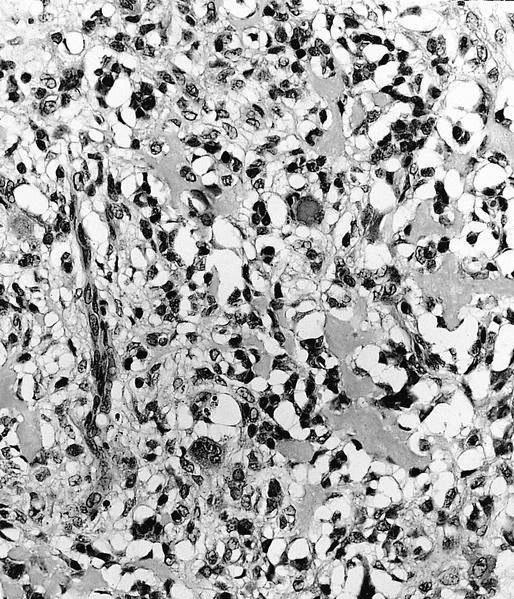

- Telangiectatic osteosarcoma: the tumor is multiloculated with large blood filled spaces; high grade malignant cells and neoplastic bone in septa (the imaging differential diagnosis is with aneurysmal bone cyst)

Microscopic (histologic) images

Contributed by Jesse Hart, D.O., Borislav A. Alexiev, M.D. and AFIP